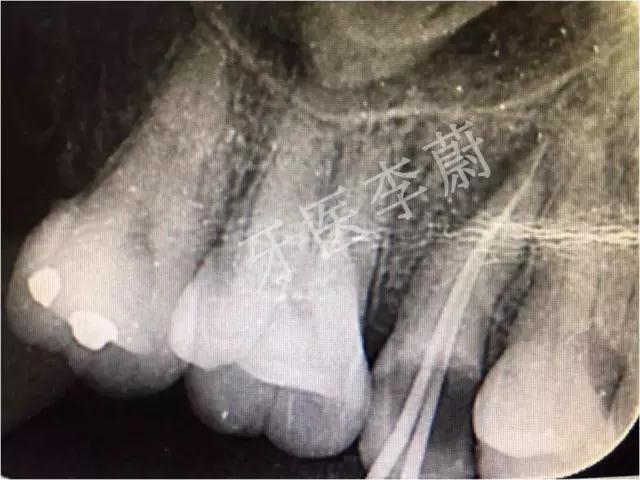

X片示:15残冠影,根尖有骨密度降低影。

局部X牙片

15牙根管充填术后X牙片